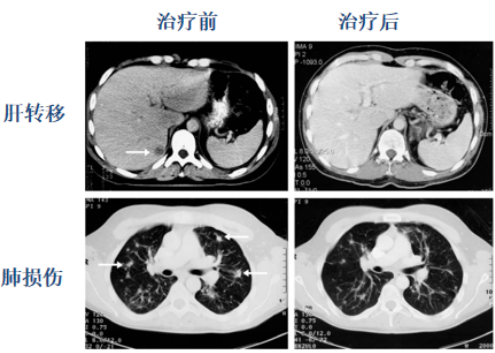

NK-T回输治疗后肺癌病人肝转移完全消退(上)肺损伤明显减少(下),箭头所示回输治疗之前的损伤部。